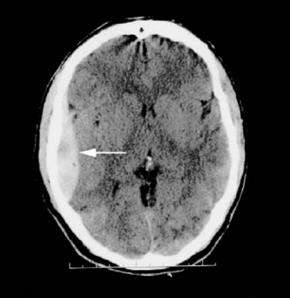

Disponível em: < http://files.bvs.br >. Acesso em: 10 jan. 2021.

Os hematomas peridurais, conforme observado na imagem, são relativamente incomuns, presentes apenas em 1% dos casos de traumatismo cranioencefálico (TCE), e apenas 10% apresentam rebaixamento do nível de consciência. Quanto aos hematomas peridurais, assinale a alternativa correta.